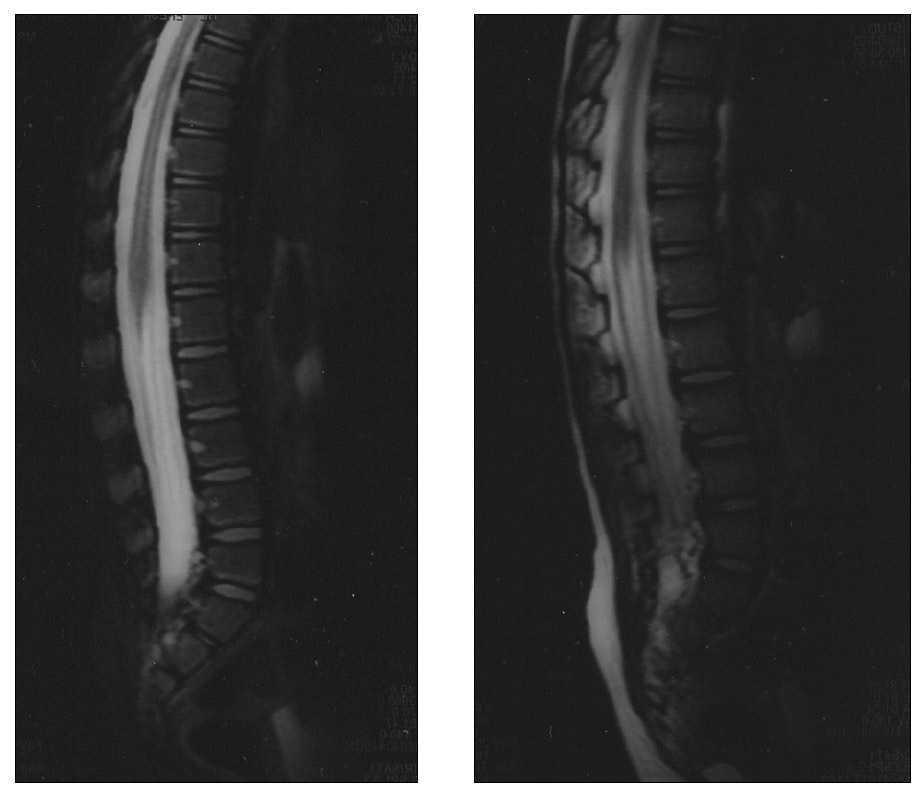

Varón de 3 años, previamente sano, que inicia dolor lumbar y de miembros inferiores que le dificulta la deambulación. Afebril. En la exploración practicada en su Centro de Salud a los 5 días de iniciado el cuadro el paciente se mostraba irritable con dolor a la extensión y rotación de ambos miembros inferiores y flexión cervical anterior (signos meníngeos). La movilidad estaba conservada en los 4 miembros. No presentaba signos de inflamación articular, siendo los reflejos miotáticos difíciles de valorar por la resistencia del paciente a la exploración. Resto de exploración física normal. Es remitido al hospital de referencia para completar evaluación diagnóstica y tratamiento. Durante su ingreso el dolor se incrementó, imposibilitando la bipedestación y se objetivó la ausencia de reflejos miotáticos en miembros inferiores. Se practicaron las siguientes exploraciones complementarias: hemograma y bioquímica en valores normales; RM medular: engrosamiento distal medular, con captación de contraste de la cola de caballo y las raíces nerviosas; LCR: proteínas 140,5 mg/dl; glucosa 65,9 mg/dl; células 5/μl (100 % linfocitos). El electromiograma fue compatible con neuropatía sensitivomotora, con disminución de la velocidad de conducción motora en nervio sural (22 m/s) y una onda F con latencia aumentada en ciático poplíteo (fig. 1).

Figura 1.RM medular sagital T1 tras administración de contraste, en la que se aprecia engrosamiento distal medular, con captación de contrase de la cola de caballo y las raíces nerviosas.

La RM es la prueba de imagen más rentable para descartar patología del raquis o del canal medular en este contexto clínico. En algunos casos de SGB, como en nuestro paciente, se observa, durante la fase aguda, la presencia de alteraciones consistentes en engrosamiento y captación de contraste en las raíces nerviosas 7,8, que coincide con la distribución del dolor 7. Estas alteraciones disminuyen progresivamente de modo paralelo a la mejoría clínica 8.